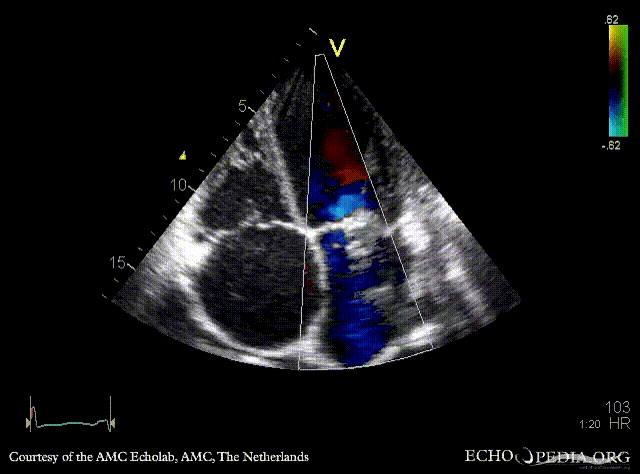

E00454.gif E00455.gif

A4CH: prolaps of PMVL, enlarged left and right atrium, poor function of dilated right ventricle A4CH: Color doppler, severe mitral regurgitation